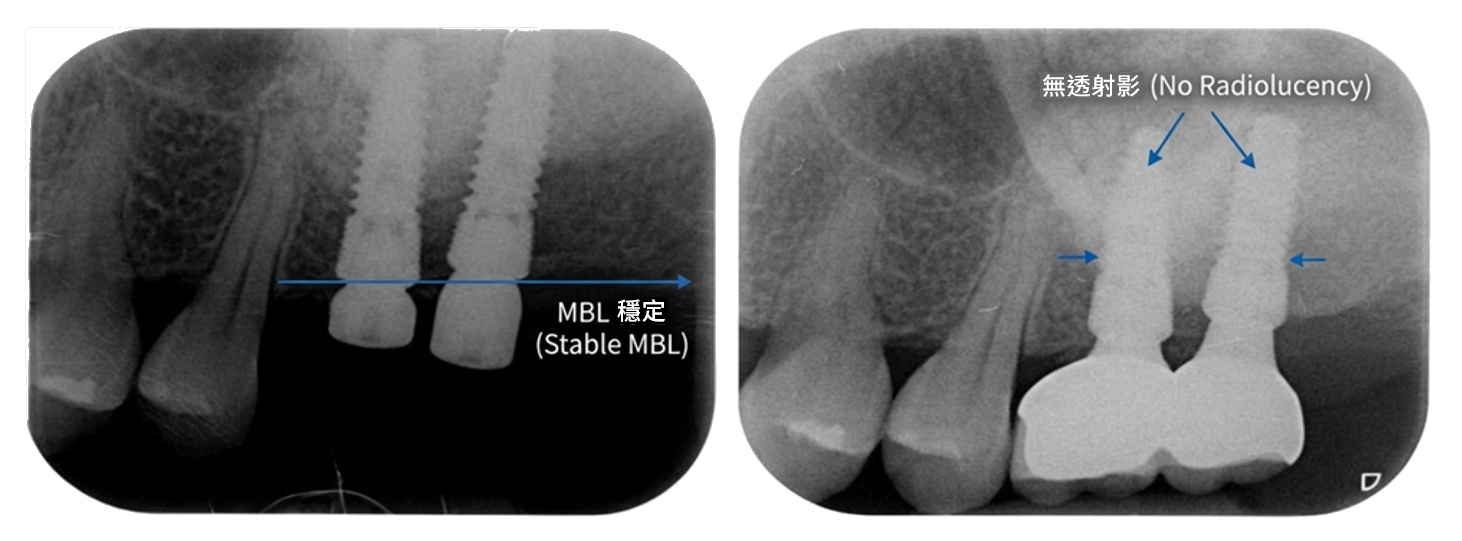

• 影像資料規範: 需提供指定之術前、術後或相關影像資料,並符合基本判讀清晰度。

影像需符合活動審查所需之基本辨識與判讀條件。